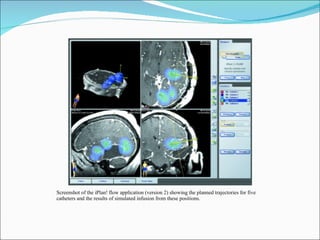

Screenshot of the iPlan! flow application (version 2) showing the planned trajectories for five catheters and the results of simulated infusion from these positions.

Screenshot of theiPlan! flow application (version 2) showing the planned trajectories for five catheters and the results of simulated infusion from these positions.